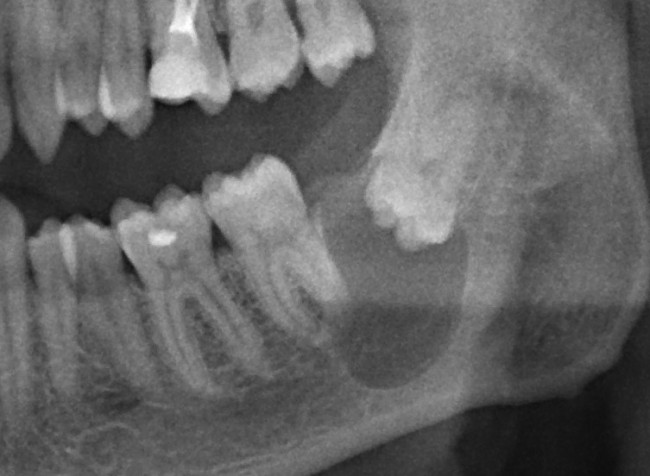

Итак, удаляем зуб и кисту.

Это занимает, в общей сложности, около получаса: 10 минут на удаление зуба, еще 15 минут на удаление кисты и наложение швов.

2

Представьте себе — 30 минут. И все. Нет никаких угроз здоровью.

После операции в таких случаях совершенно обычными являются отек, незначительные болезненные ощущения и т. д. Пациент получает стандартные рекомендации по послеоперационному режиму, курс антибактериальной противовоспалительной терапии и остается полностью работоспособным.

Повторюсь: РАБОТОСПОСОБНЫМ! А это значит, что ни стационар, ни больничный лист после таких операций, чаще всего, не нужны.